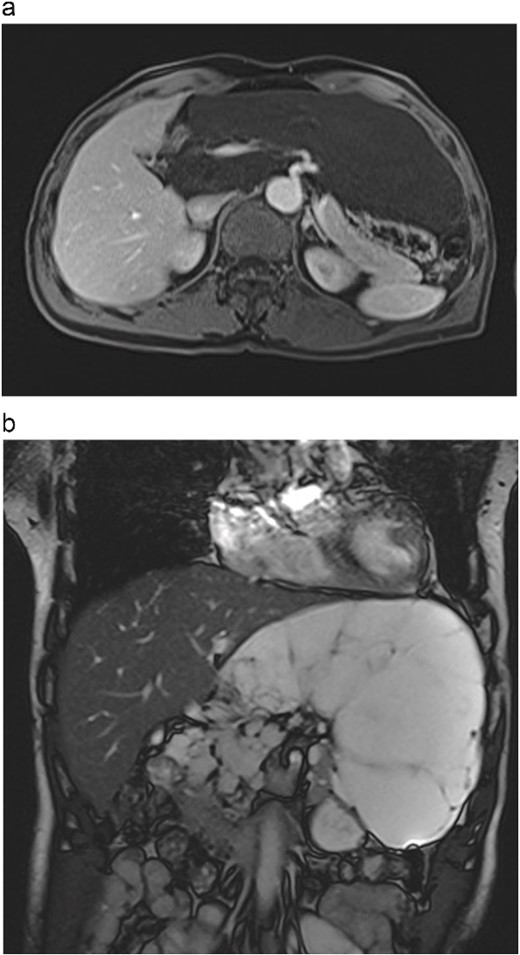

A 66-year-old male was admitted on 15th July 2024 due to an abdominal mass detected two months earlier. Physical examination revealed a soft, non-tender abdominal mass with limited mobility in the left upper abdomen. Abdominal MRI showed a large, irregular mass in the retroperitoneal space measuring ⁓19 cm × 8 cm with clear borders and multiple internal septa. The mass was compressing surrounding structures, including the portal vein, common hepatic artery, and coeliac trunk (Fig. 1a and b).

(a) Abdominal contrast-enhanced scan in the arterial phase shows the tumour compressing the portal vein, common hepatic artery, and celiac trunk. (b) T2-weighted MRI image shows the tumour with high signal intensity and no solid components.